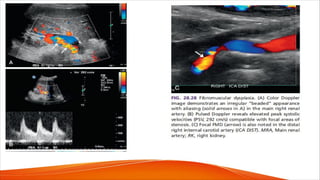

FIG. 28.27 Fibromuscular dysplasia.

(A) Gray-scale image demonstrates

multiple saccular dilatations

(solid arrows in A) in the hilar portion of

the main renal artery.

(B) Color Doppler image shows

disturbed flow and aliasing at the areas

of narrowing (dashed arrows in B)

between the aneurysmal

dilatations (solid arrows in B).

(C and D) Pulsed Doppler waveforms

from the narrowed segments show

elevated peak systolic velocities (PSV,

235 cm/s in C; 267 cm/s in D)

compatible with focal

stenoses. DIST, Distal; RRA, right renal

artery